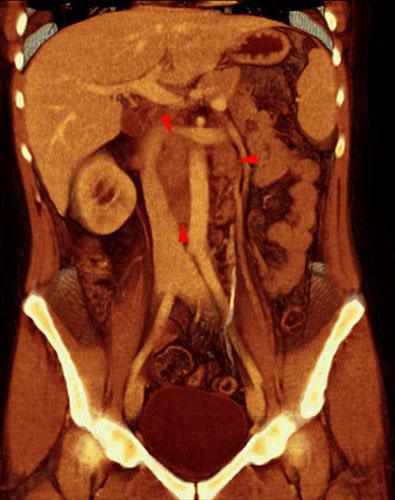

Carcinoma medular renal

VR seccional. Visión coronal anterior. Adenopatías retroperitoneales interaortocava y paraaórticas izquierdas (puntas de flecha). Obsérvese el desplazamiento lateral de la vena cava inferior